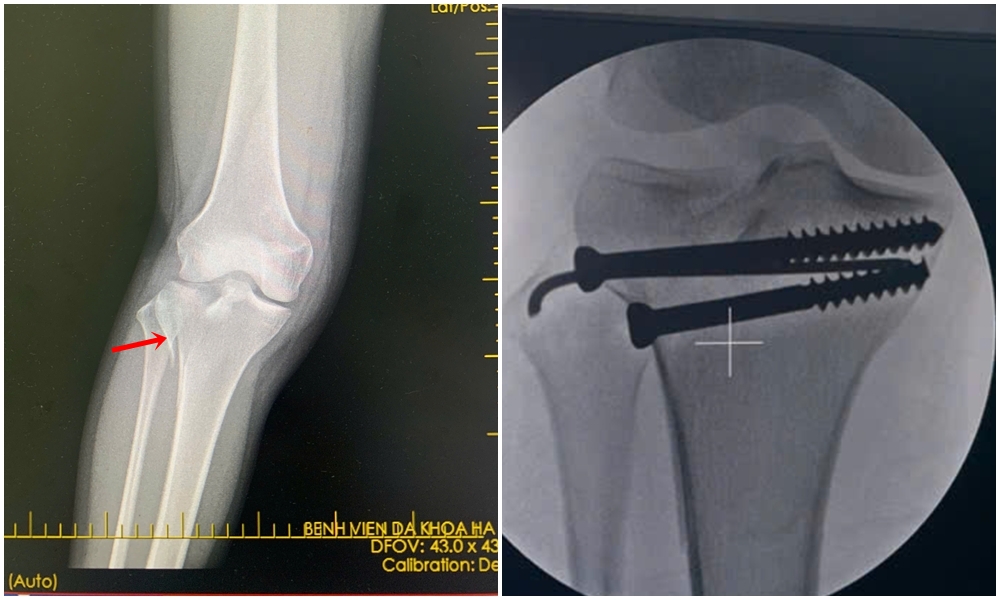

Bệnh nhân là Đ.T.D (29 tuổi, ở xã Thống Nhất) bị tai nạn giao thông, được đưa vào cơ sở 2 Bệnh viện Đa khoa tỉnh (Bệnh viện Đa khoa Hạ Long cũ) cấp cứu. Qua thăm khám và chụp X-quang đánh giá, bác sĩ chẩn đoán bệnh nhân bị vỡ lún mâm chày ngoài chân phải. Đánh giá đây là tổn thương cần được phẫu thuật sớm, hạn chế di chuyển để tránh ảnh hưởng đến khả năng vận động của người bệnh, Ban Giám đốc Bệnh viện Đa khoa tỉnh đã chỉ đạo đội ngũ chuyên gia từ cơ sở chính di chuyển đến cơ sở 2 để tăng cường nhân lực phẫu thuật.

Qua đường rạch da nhỏ chỉ 1cm, phẫu thuật viên nắn chỉnh ổ gãy về đúng vị trí giải phẫu, sau đó cố định xương bằng vít xốp chuyên dụng, giúp đảm bảo sự vững chắc của khớp gối đồng thời giảm thiểu sang chấn phần mềm, rút ngắn thời gian phục hồi sau mổ. Ca phẫu thuật diễn ra thuận lợi trong vòng một giờ, bệnh nhân tỉnh táo, ít đau, chân nẹp vít có thể cử động được sau mổ và đang tiếp tục theo dõi chăm sóc.

Hình ảnh X-quang bệnh nhân bị vỡ lún mâm chày ngoài chân phải trước và sau phẫu thuật kết hợp xương ít xâm lấn bằng vít xốp.